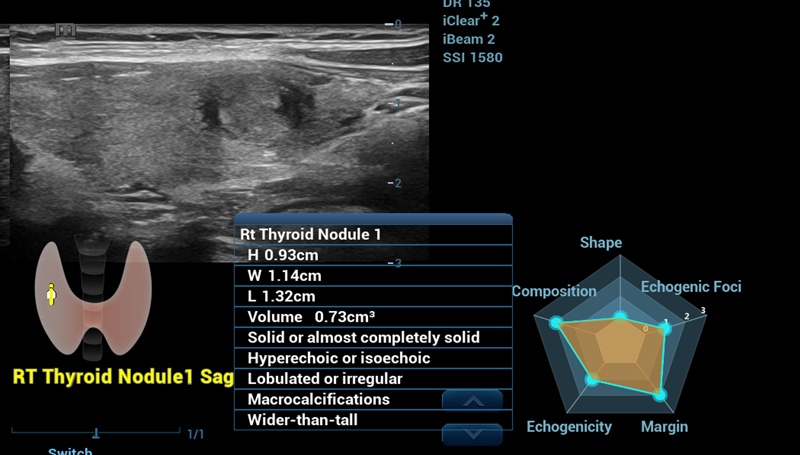

Smart Thyroid

Un altro piano, un'altra visuale

Smart Thyroid

Thyroid Ăš uno strumento di analisi e refertazione della tiroide che rende la routine clinica degli esami tiroidei piĂč accurata e produttiva.

Smart Thyroid nodulo